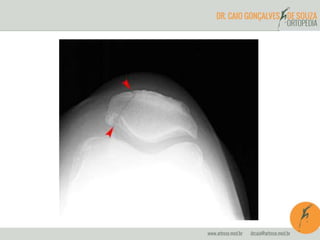

Diagnóstico por Imagem

• Raio-x

– Baixa acurácia no diagnóstico da condromalácia

– Patela alta

Condromalacia Grau I

Condromalacia Grau II

Condromalacia Grau III

Condromalacia Grau IV